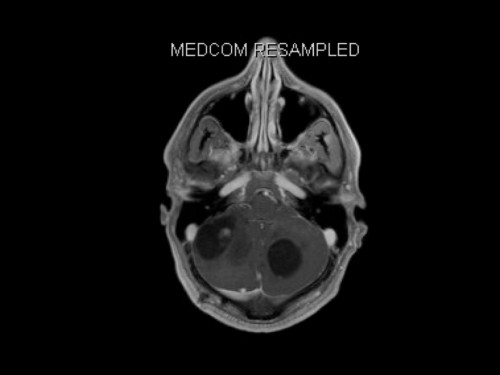

3. Schwindel und Kopfschmerzen, 3 Jahre nach Phäochromozytom-Resektion

Schwindel und Kopfschmerzen, 3 Jahre nach Phäochromozytom-Resektion

19-jähriger Mann. Er klagt seit mehreren Wochen über Schwindel und Kopfschmerzen. Im Alter von 16 Jahren sind er und sein Zwillingsbruder an einem Phäochromozytom operiert worden.